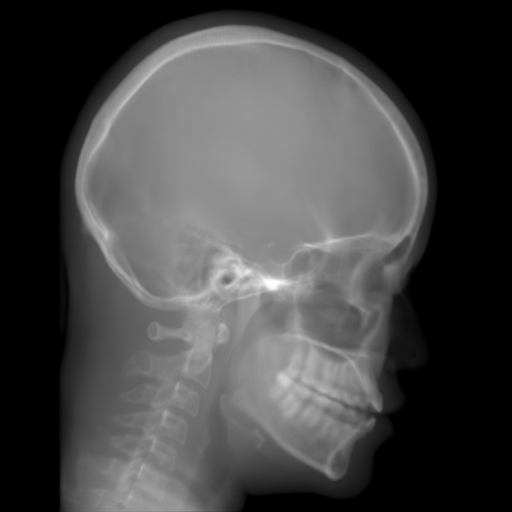

The results of one exemplary patient for cephalometric imaging are displayed in Fig. 11. In the 0superscript00^{\circ} perspective projection image (Fig. 11(b)), because of perspective deformation, anatomical structures from the left and right sides do not overlap well, especially for the mandible as indicated by the red arrow in Fig. 11(b). It causes inaccuracy in determining the cephalometric landmark of the gonion. The difference of Fig. 11(b) to the reference Fig. 11(a) is displayed in Fig. 11(c). A scale bar of 2 mm is displayed in Fig. 11(c), as 2 mm is the clinically acceptable precision for cephalometric landmark detection. It is obvious that many anatomical structures in the 0superscript00^{\circ} perspective projection images have position shifts larger than 2 mm. In the prediction image (Fig. 11(d)) using a single 0superscript00^{\circ} view in Cartesian coordinates, perspective deformation is reduced to some degree, as displayed in the difference image Fig. 11(g). For example, the mandible region has less error. However, Fig. 11(g) also indicates that many bony structures still have deviations larger than 2 mm. The results of learning from dual complementary views in Cartesian and polar coordinates are displayed in Fig. 11(e) and Fig. 11(f), respectively. Both images have little perspective deformation, as revealed by their difference images in Fig. 11(h) and Fig. 11(i). Nevertheless, in Fig. 11(e), two dark regions are indicated by the two arrows, which are better visualized in the difference image Fig. 11(h). The results of TransU-Net are displayed in Figs. 11(j)-(o). In Fig. 11(m), the structures near the porion landmark are distorted, for example, the ear canal indicated by the arrow. Consistent with Pix2pixGAN, perspective deformation is largely reduced in the both TransU-Net prediction images using dual complementary views in Cartesian and polar coordinates.

Figure 11: Perspective deformation learning in one exemplary patient case for cephalometric imaging. In (b), the left and right sides of the mandible do not overlap well, as indicated by the arrow. In (c), a scale bar of 2 mm is displayed (zoom in for better visualization), as 2 mm is the clinically acceptable precision for cephalometric landmark detection. In (e), (h) and (j), incorrect areas are marked by the red arrows.